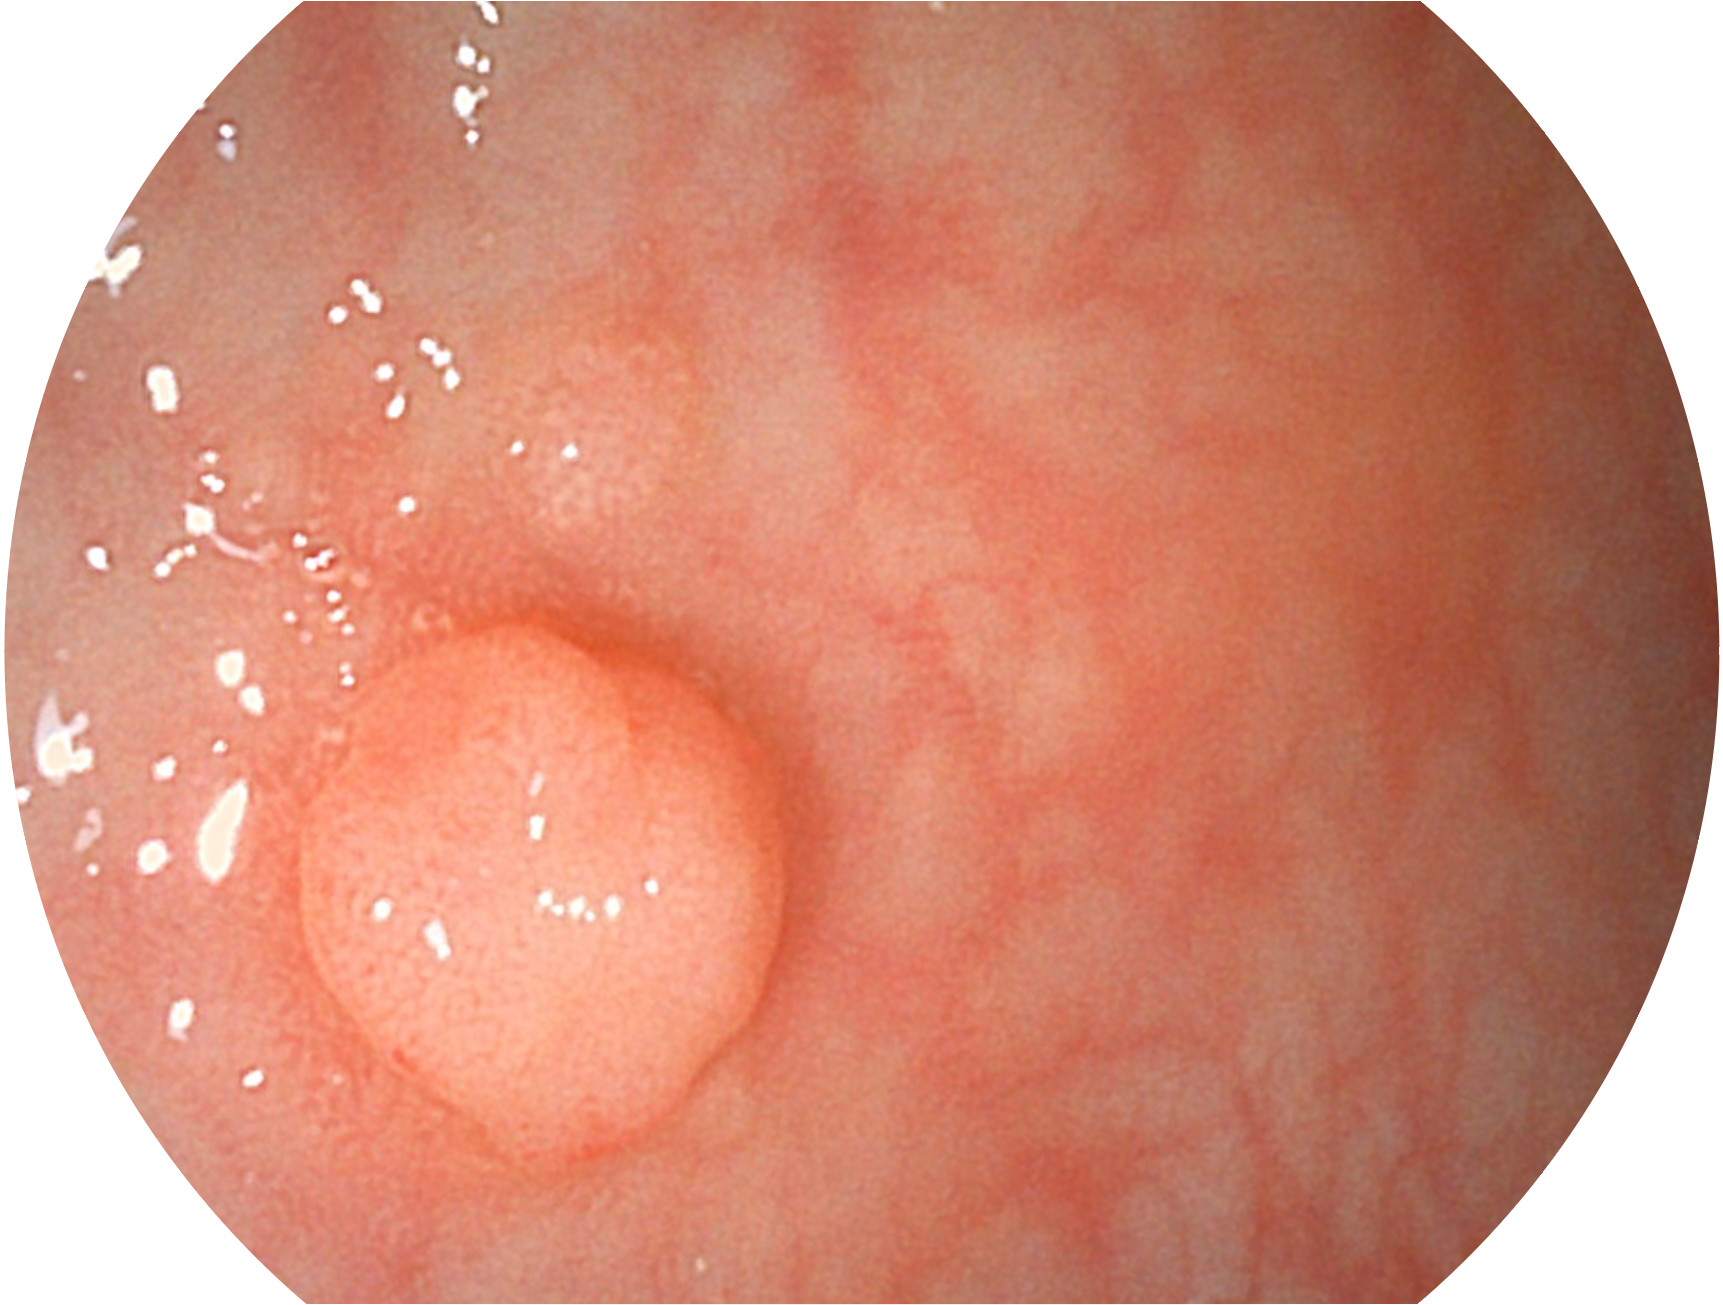

百老汇电子游戏官网新开发的内镜染色技术,主要是基于多波长LED 光源的开发,VLS-55Q 四波长LED 光源是由四个不同颜色的LED光按照相应照明模式所规定的特定发光比例进行合束后形成,合束后形成的照明光的光谱由红光、绿光、蓝光及蓝紫光这四个不同的波段范围构成。具有更高光谱自由度,通过光谱比例的控制,实现了聚谱成像技术,英文全称为“Spectral Focused Imaging, SFI”,缩写为“SFI”和光电复合染色成像技术,英文全称为“Versatile Intelligent Staining Technology, VIST”,缩写为“VIST”。